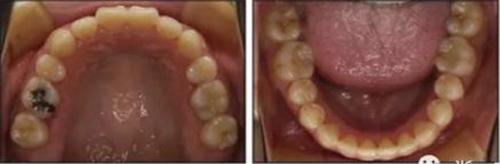

2.檢查:凸面型、骨性II類,安氏II類1分類錯合畸形。面型正中對稱,下面高略高,頦部后縮,唇肌略緊張。無顳下頜關(guān)節(jié)癥狀,下頜運(yùn)動正常,無偏斜。上下頜中線與面中線相一致,所有恒牙存在,口腔衛(wèi)生可,牙周情況可。患者健康,無系統(tǒng)性疾病,無牙科創(chuàng)傷史及不良習(xí)慣,懷疑遺傳因素導(dǎo)致錯合畸形。

3.測量分析:治療前記錄提示該患者左右磨牙與尖牙為安氏II類關(guān)系,上頜牙弓重度擁擠,下頜牙弓輕度擁擠,深Spee曲線。6.3mm深覆蓋,80%深覆合。牙齒無齲,無第三磨牙。